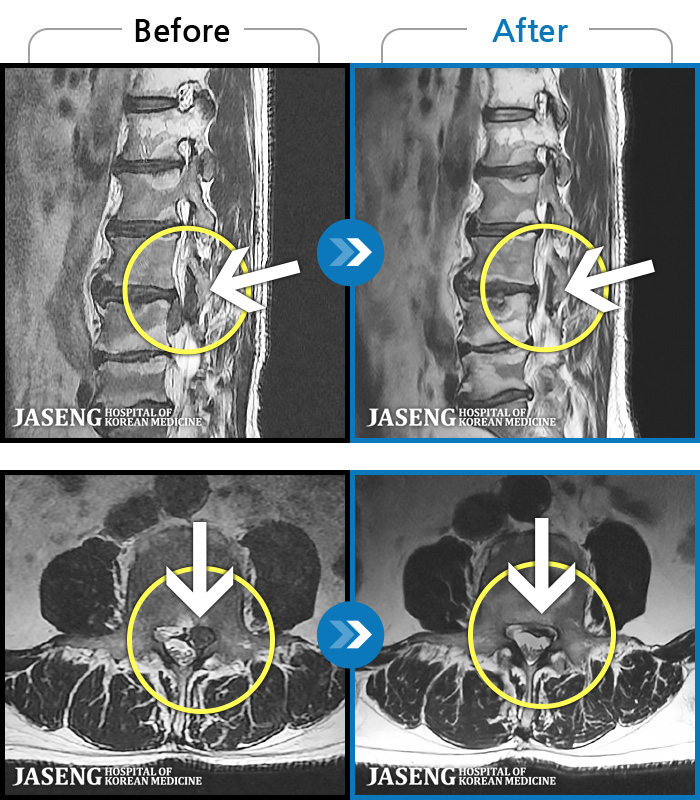

MRI ġ

1,251 MRI ũ ʸ Ȯϼ.